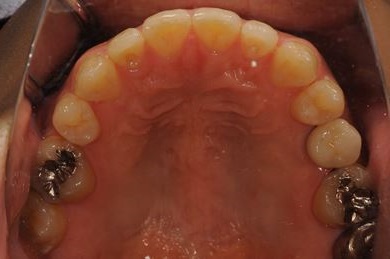

インプラントの症例写真 IMPLANT

骨再生インプラント治療

| 性別/年齢 | 男性 / 34歳 | ||||||||||||||||||||||||||||||||

| 治療方針 | ソケットリフトにて上顎洞を拳上し、インプラント治療を可能にする。 | ||||||||||||||||||||||||||||||||

| 治療内容 | インプラント1本(ソケットリフト)、メタルボンドセラミッククラウン1本 | ||||||||||||||||||||||||||||||||